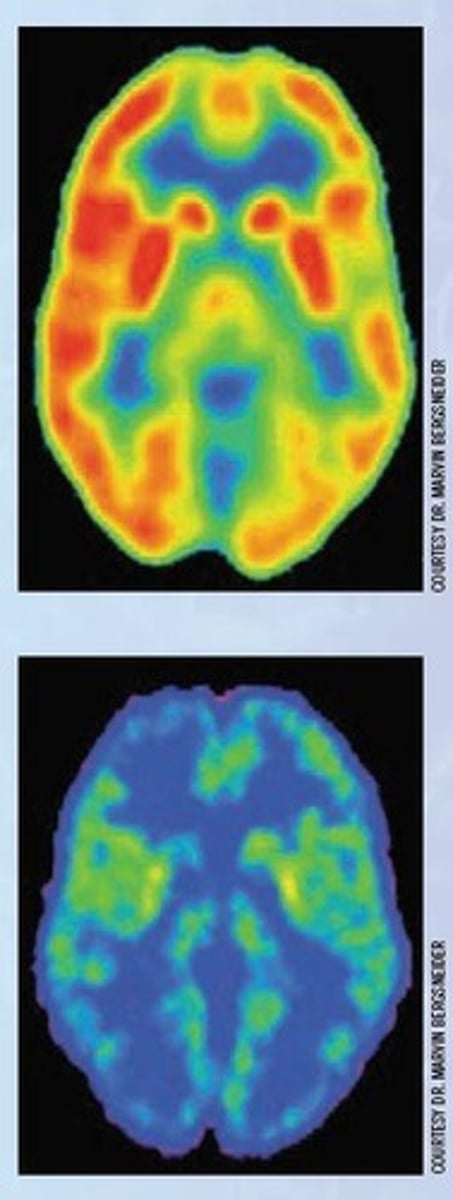

What brain changes were observed in L.D. after his injury?

Damage to both sides of the brain and decreased glucose flow, indicating atrophy.

To combine brain imaging techniques (like PET scans) with cognitive tests to diagnose conditions such as mild cognitive impairment or early dementia.